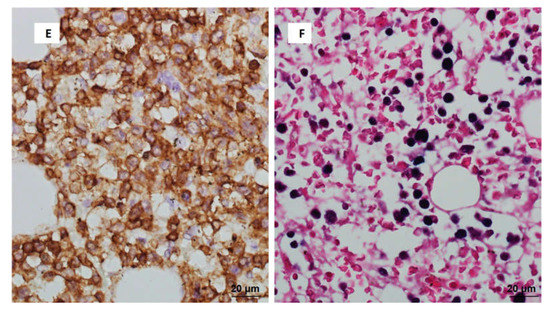

3. Discussion

3.1. T/NK-Cell PTLD